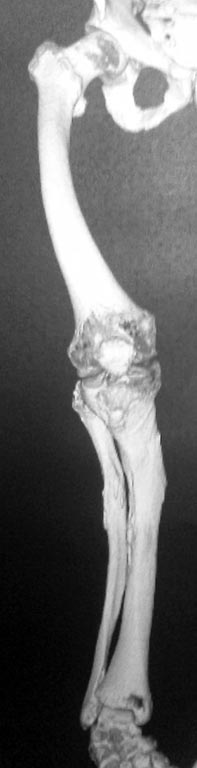

Помогите разобраться с переломом бедра у непростого пациента.

Молодой пациент (абсолютно социален и адекватен), рост около 140 см,

бедро 20 с небольшим, по механической оси. Низкоэнергетическая травма,

судя по записям в амбулаторной карте - несколько раз оперировался по

поводу болезни Блаунта в детстве на голенях, сведений и следов

операций на бедрах нет. Рассматриваем несколько вариантов остеосинтеза:

3. ЧКО Нужно ли резецировать зону перелома при последних двух вариантах

(выглядит как псевдоартроз)? Любые соображения, варианты приветствуются,

сожалею за снимки, лучше не получилось.